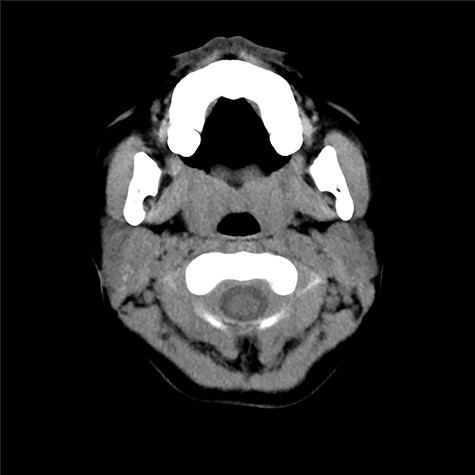

Three and a half years after the initial surgery, she presented with high fever and painful swelling of her right parotid area (Fig. 5). CT scan presented swelling of the parotid gland (Fig. 6). No cystic structure could be pointed out. Under general anesthesia, incision, cleansing and drainage were done. Staphylococcus aureus was identified in the pus. Decline of fever was obtained and remission of the abscess was seen.

Cystic lesion could not be observed by CT scan prior to the drainage.